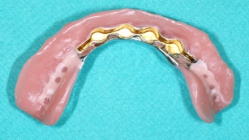

Since 1992, titanium screw implants have been inserted in edentulous sections of the upper and lower jaw in the clinic. Such dental implants serve as artificial tooth roots which, in combination with a tooth-crown-like superstructure (superstructure), enable the restoration of isolated tooth gaps with a crown, in the case of several missing teeth with a crown block, and finally in the case of an edentulous jaw with a fixed prosthesis.